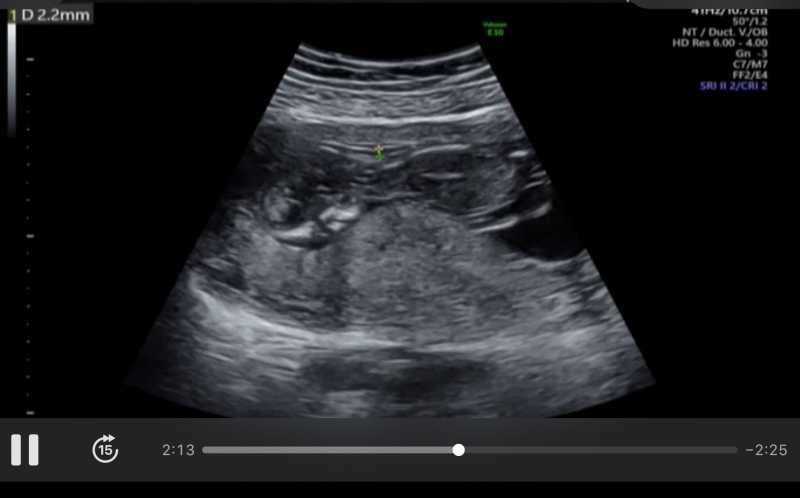

13週の検診時のエコー写真です。

先生からは何も指摘などされてませんが、高齢出産ということもあり、浮腫など気になっています。

浮腫を計ってるのでしょうか?

お写真からですと、ハッキリとは分からないのですが、お子さんの身体とは別の部分を計測しているようにお見受けします。ですので、もしかすると、お子さんの周りの羊水量などを見ているのかもしれません。また、浮腫など、何か気になる所見がある場合には、必ず医師から説明があるかと思いますので、今の時点で何も指摘されていないのであれば、経過は順調とお考えいただいて問題ないと思いますよ。ハッキリとしたことが明言できず、申し訳ありませんが、もしご心配であれば、また健診の際にご確認なさってみてくださいね。